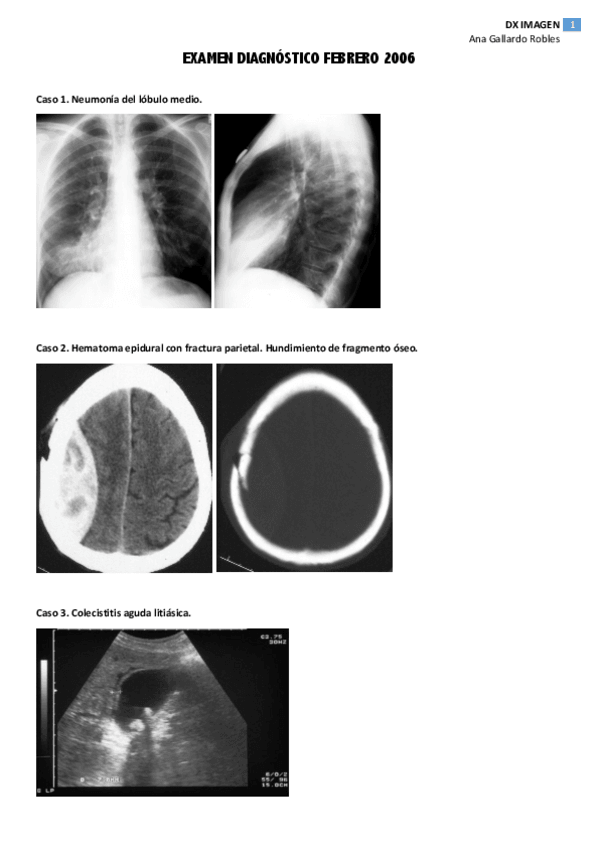

examen 2006 .pdf

3 páginas